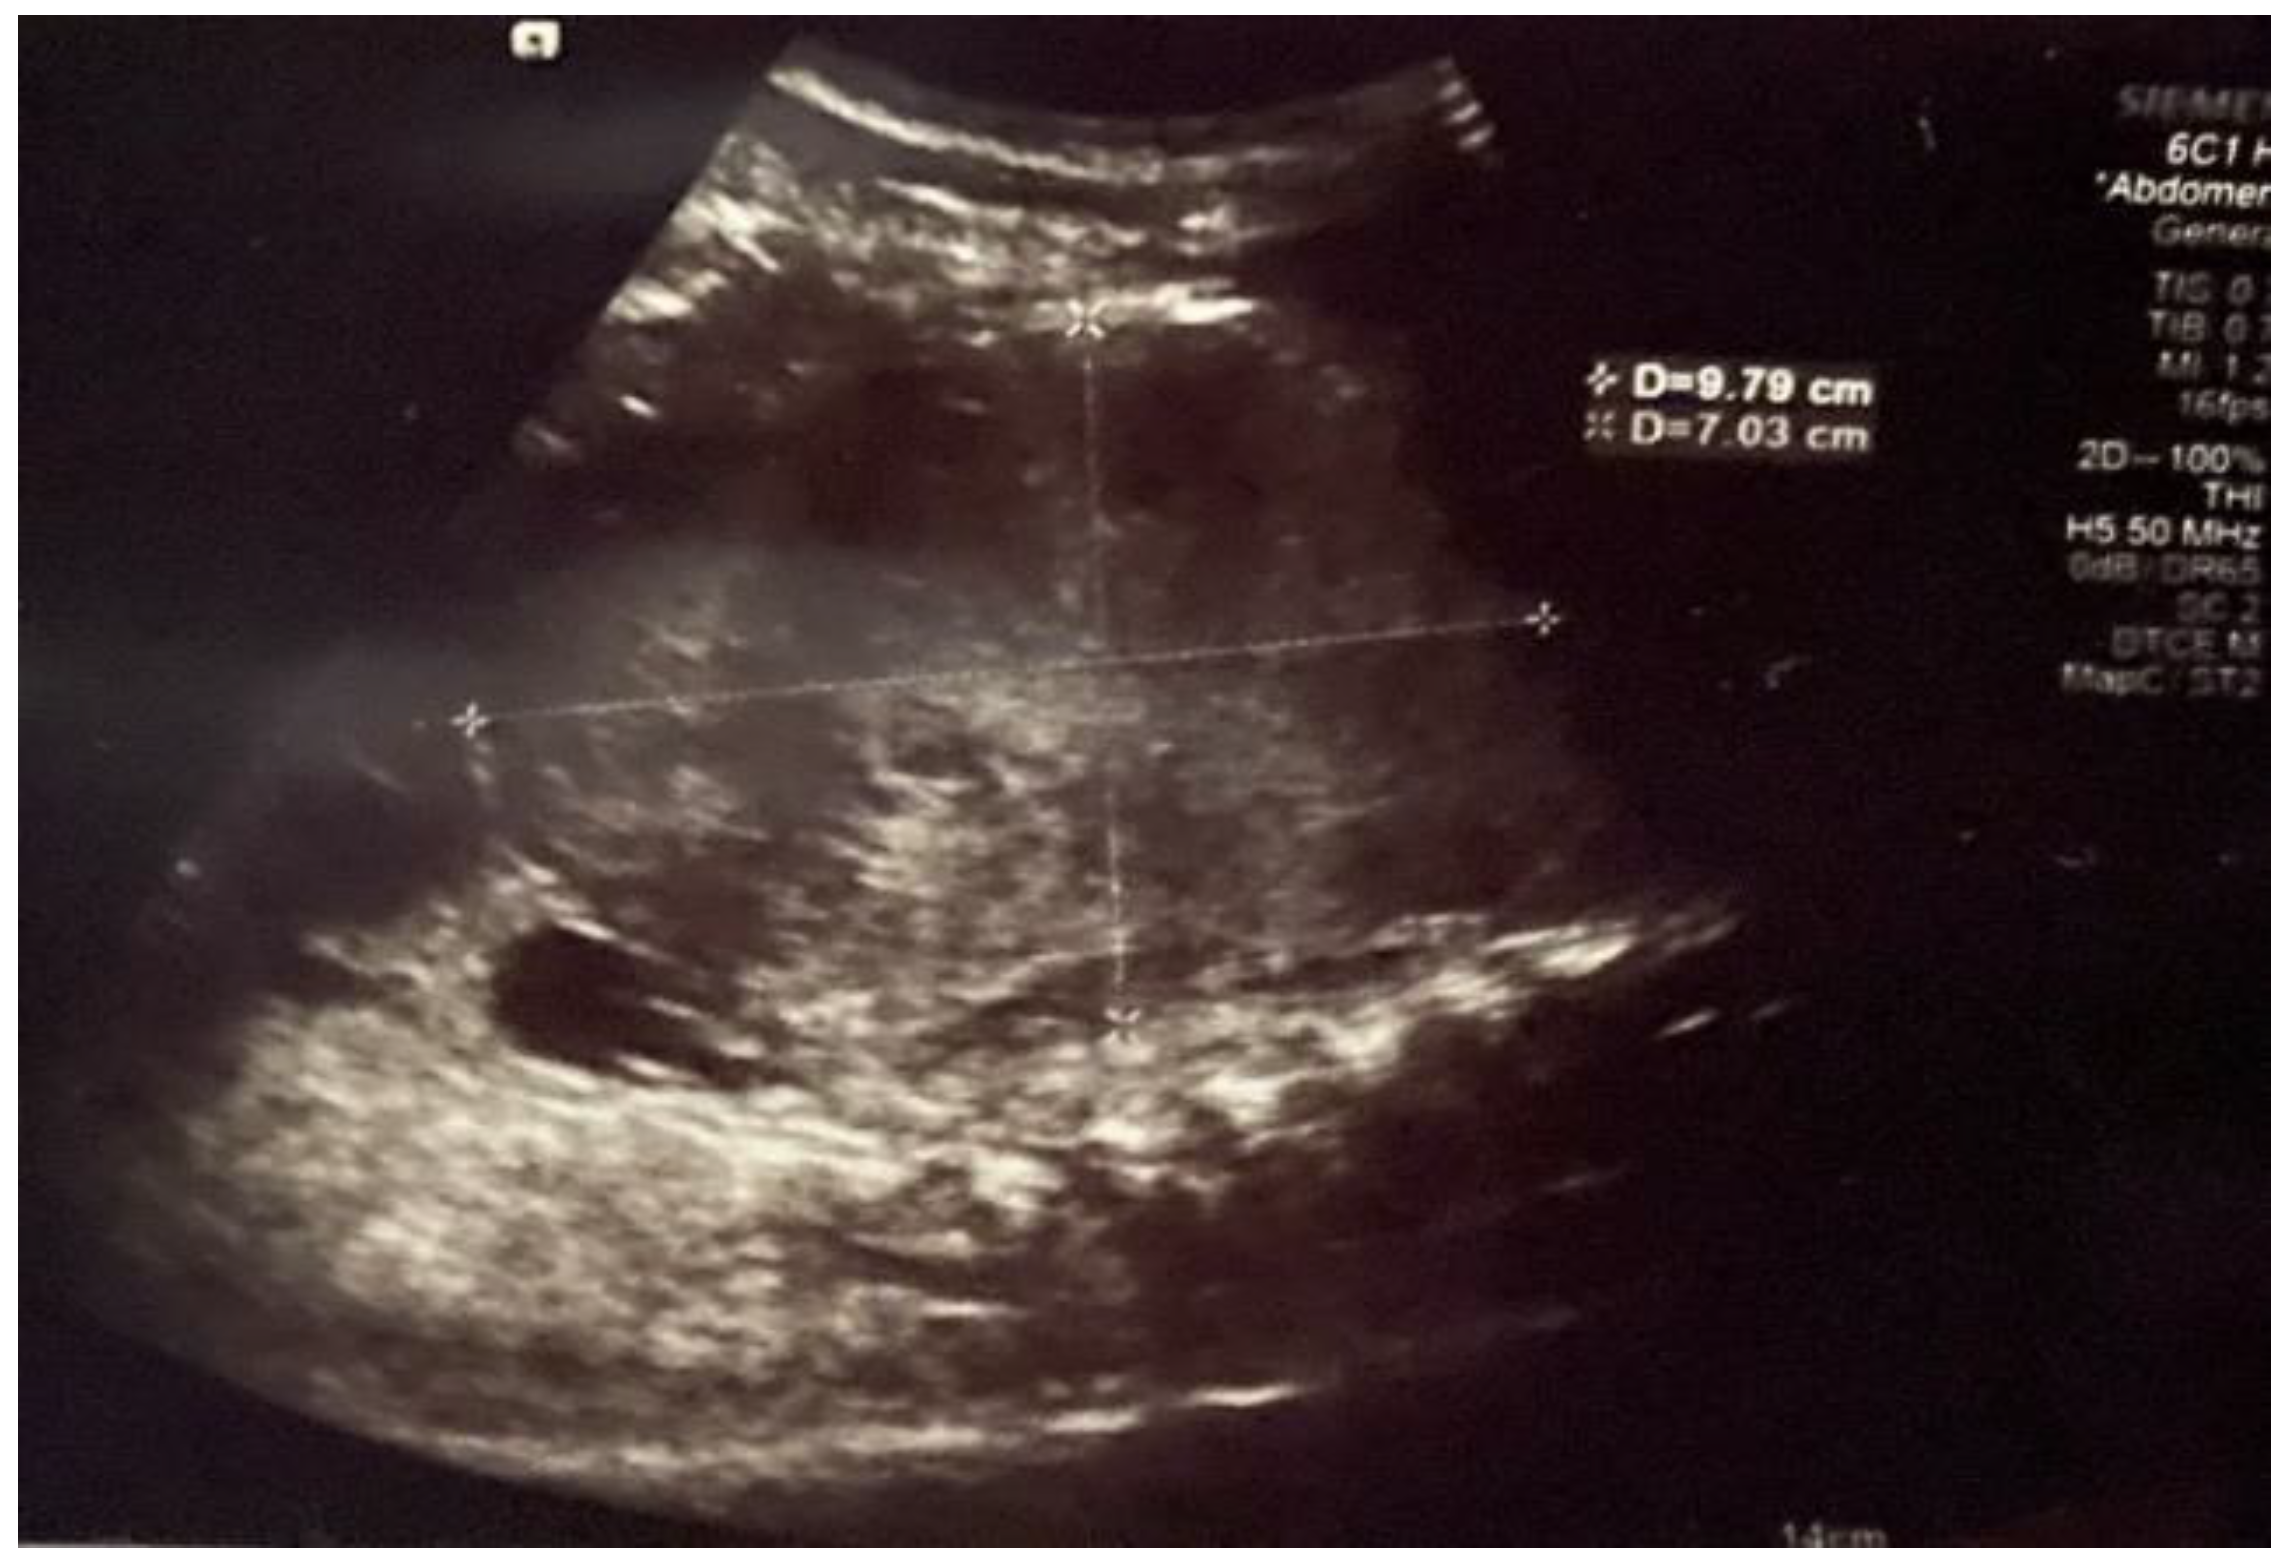

Initial abdominal ultrasound (US) revealed a large abdominal mass occupying the upper and middle aspect of the abdomen, probably of liver origin (Figure 1).

Initial abdominal ultrasound showing a large heterogeneous liver mass.